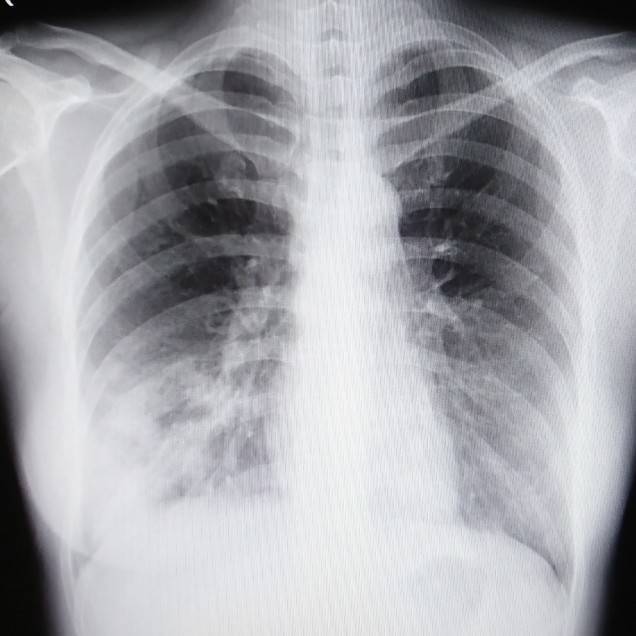

ここで突然ですが写真を見てみましょう。

胸部の一般撮影です。

どうですか?

肺炎は見つかりましたか?

答えはココです。

レントゲンでは見慣れないとなかなか見つけづらいですよね。